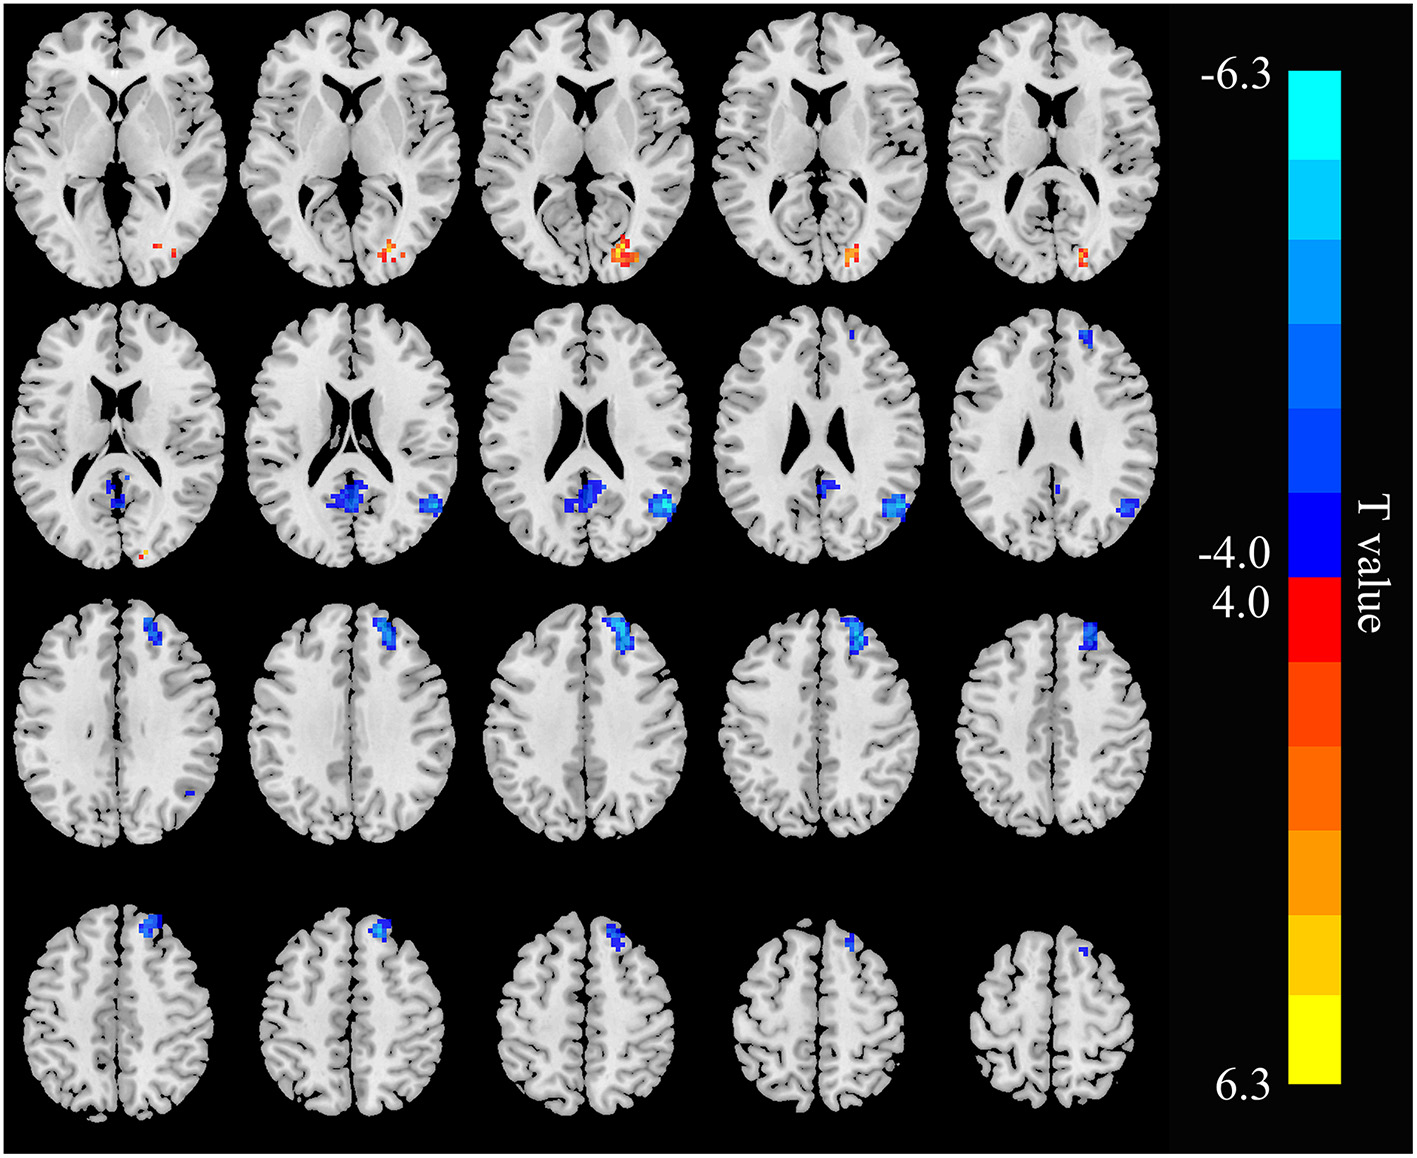

The three seed ROIs, in which increased/decreased ALFF values were found in hemodialysis patients with ESRD, were chosen for FC analysis. Relative to the control group, the patient group showed decreased connectivity between the RAG and the left precuneus, right superior frontal gyrus (RSFG), but increased connectivity between the RAG and right cuneus; the connectivity within the RAG was weak (Figure 4; Table 3). In addition, connectivity between the right precuneus and left supramarginal gyrus was enhanced in the ESRD group (Figure 5; Table 4). When setting the right precentral gyrus as seed ROI, patients with ESRD showed no significant functional connection abnormality in the whole brain. There was no correlation between the Z scores of abnormal FC regions and any clinical data in patients.

Figure 4

Functional connectivity (FC) differences in the right angular gyrus between patients with ESRD and HC (p < 0.05, FDR corrected). Patients with ESRD show reduced connectivity between the right-angular gyrus with the left precuneus and right superior frontal gyrus, and increased connectivity between the right angular gyrus and right cuneus; the connectivity within the right angular gyrus was weak.

Table 3

| Brain areas | Voxel | Peak T score | MNI coordinates | ||

|---|---|---|---|---|---|

| x | y | z | |||

| Right angular gyrus | 87 | −6.2459 | 54 | −60 | 24 |

| Left precuneus | 92 | −5.0333 | 0 | −60 | 21 |

| Right superior frontal gyrus | 182 | −5.272 | 21 | 48 | 39 |

| Right cuneus | 56 | 4.9689 | 24 | −78 | 9 |

Brain areas showing altered FC with the right angular gyrus in patients with ESRD.

Figure 5

Functional connectivity differences in the right precuneus between patients with and HC (p < 0.05, FDR corrected). Patients with ESRD show increased connectivity between the right precuneus with the left supramarginal gyrus.

Table 4

| Left supramarginal gyrus | 84 | 4.9041 | −57 | −21 | 33 |

Brain area showing abnormal FC with the right precuneus in patients with ESRD.